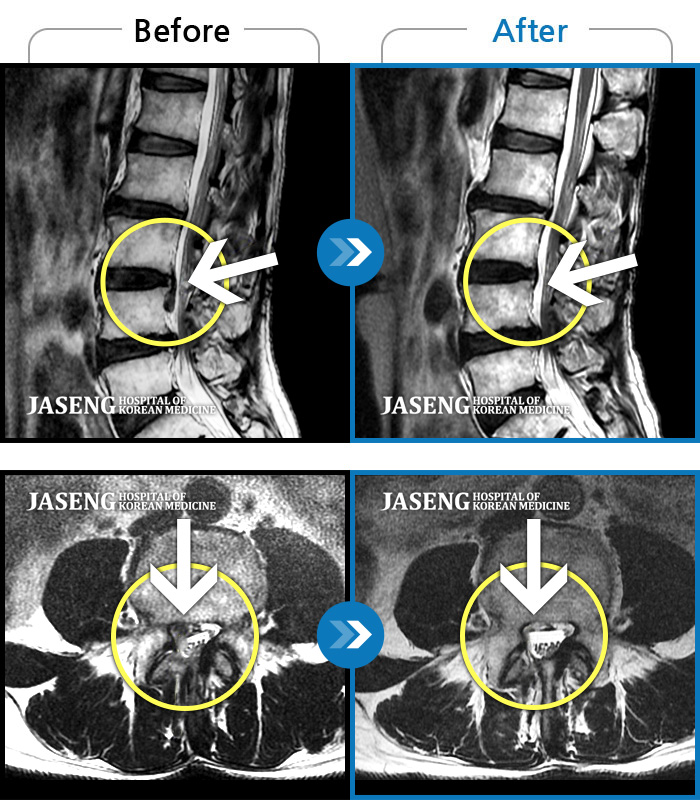

ȯںп Ǹ ǿ ԿǾ, ο ġ ۿ Ƿ ġḦ Ͻñ ٶϴ.